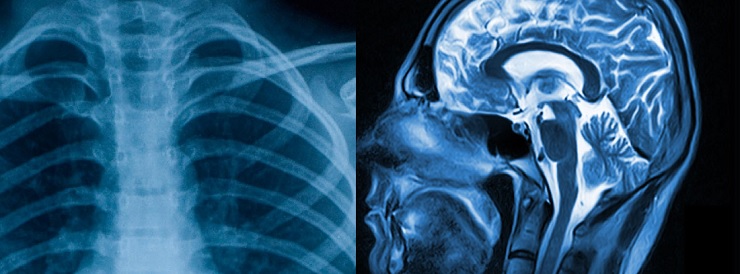

MD Radiodiagnosis किंवा Doctorate of Medicine Radiodiagnosis : हा डॉक्टरेट स्तरावरील अभ्यासक्रम आहे जो 3 वर्षांच्या कालावधीसाठी आयोजित केला जातो. हे अभ्यासक्रम पॅथॉलॉजी, फिजिओलॉजी, अॅनाटॉमी इत्यादी विषयांवर केंद्रित आहेत. एमडी रेडिओडायग्नोसिसमध्ये प्रवेश घेण्यासाठी, विद्यार्थ्यांना एमसीआय मान्यताप्राप्त विद्यापीठातून एकूण किमान 55 % गुणांसह एमबीबीएस अभ्यासक्रम पूर्ण करणे आवश्यक आहे. भारतातील MD रेडिओडायग्नोसिस कॉलेजमध्ये प्रवेश घेण्यासाठी, एखाद्याला NEET PG ची प्रवेश परीक्षा उत्तीर्ण करावी लागते. या कोर्स साठी लागणारी पात्रता, व्याप्ती, अभ्यासक्रम, पगार, जाणून घेऊ या.

• न्यूरो - रेडिओलॉजी

• सामान्य रेडिओलॉजी